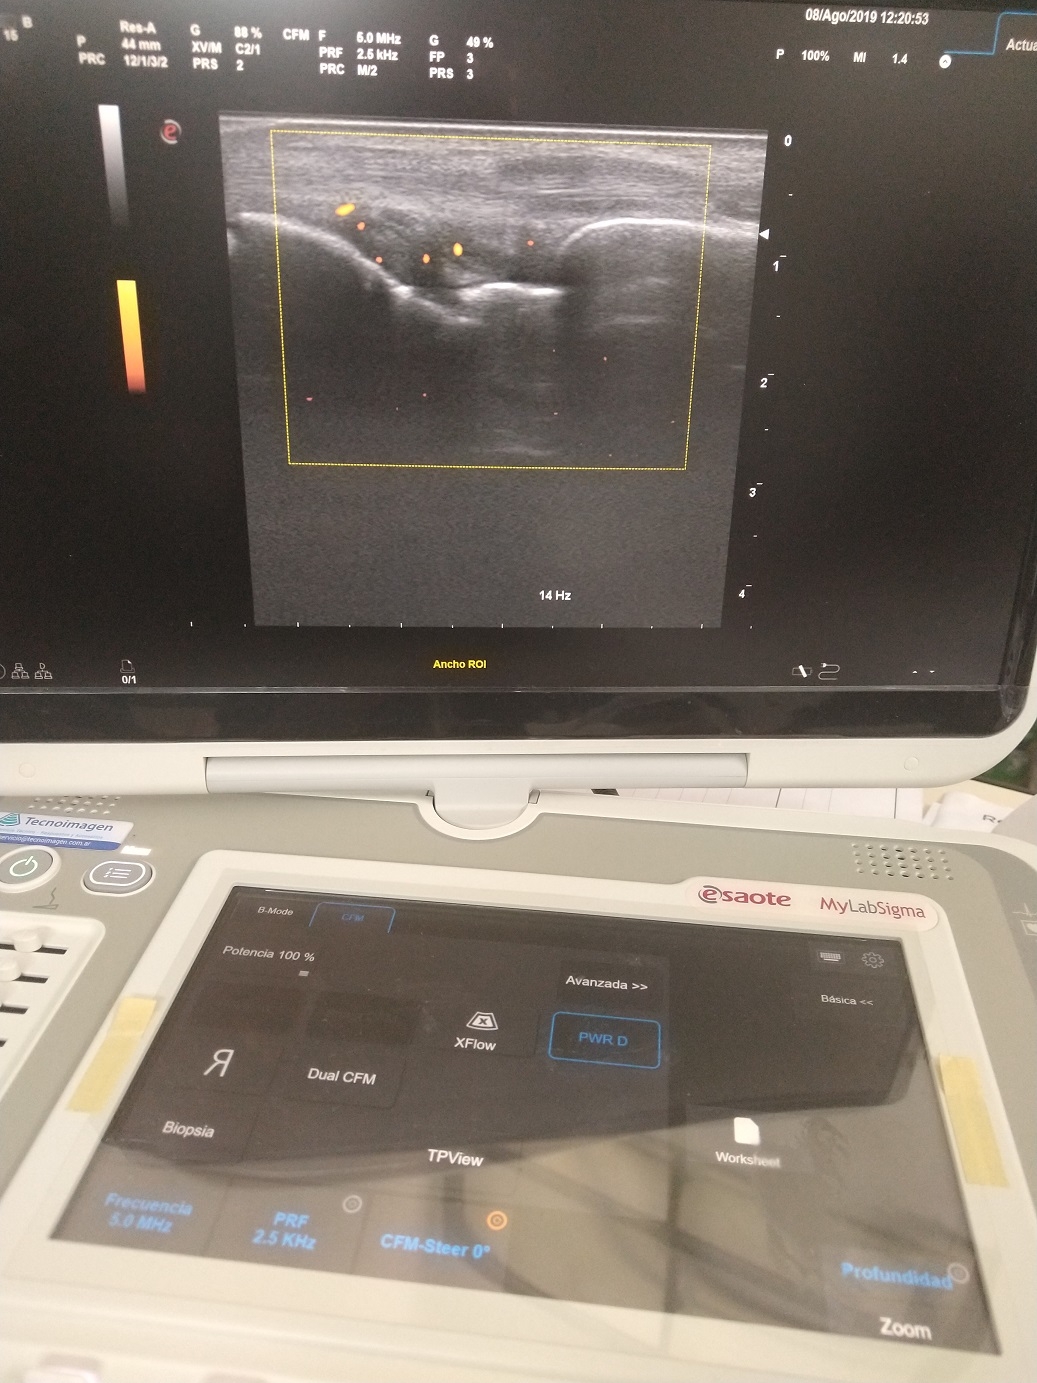

En este marco, la semana pasada el equipo de Reumatología del Hospital Interzonal San Juan Bautista, avanzó en la realización de prácticas diagnósticas, poco comunes en la provincia, para el reconocimiento de patologías asociadas a esta especialidad; en esta oportunidad se realizaron estudios de ECOPOWER para la detección de artritis temprana.

Cabe mencionar que son estudios diagnósticos complementarios que permiten ver en forma directa la inflamación de las articulaciones en manos, muñecas, tobillos, pies y rodillas, y que además, facilitan la confirmación en pacientes cuyos estudios de laboratorio no arrojan resultados decisivos, pero que, sin embargo, presentan una sintomatología que advierte la presencia de la enfermedad.